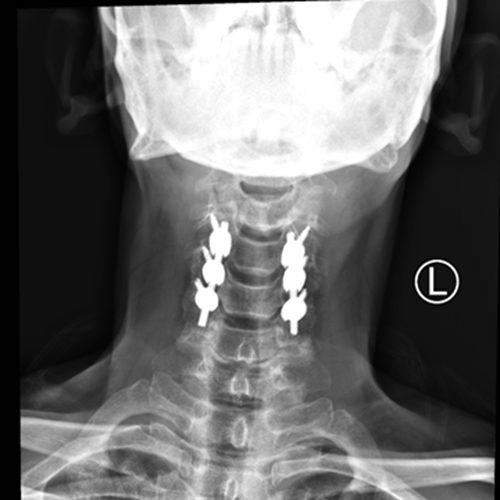

入科后,骨科主任张朝跃教授所带领团队对曾大叔进行查体,发现颈部活动受限,双上肢无法活动,双下肢无法抬离床面,仅有些许肌肉收缩,整个人呈瘫痪状态。为最大化降低创伤对患者神经功能造成的不可逆伤害,尽快恢复神经功能创造条件,经过脊柱外科组上团队讨论后,于7月3日急诊为患者在全麻下行颈椎后路椎板切除+椎管减压+钉棒系统内固定术,手术顺利。